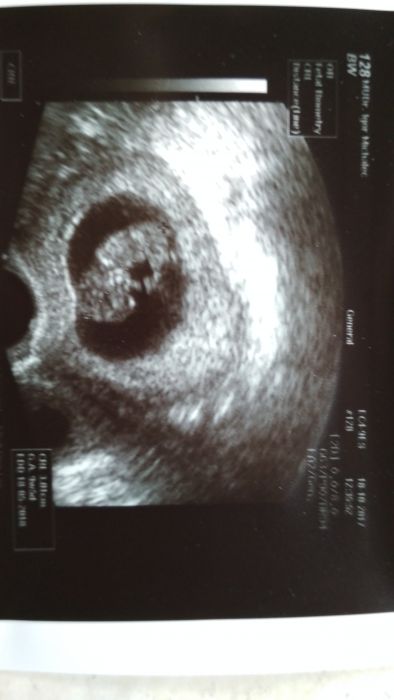

[1031678] Ahojky Sandruš a holky : no píšu až teď protože jsem u dr. Čekala asi 1,5 byl to děs , ale nakonec všechno dobrý mrně krásně roste termín zase posunut na 23.4. . Asi to bude opět kluk ;-) takze se taťka trefil .. akorád mám hodně nízko placentu tak mám být prý víc v klidu jako neskákat , neběhat , že bych mohla začít krvácet tak snad to bude v pohodě ;-) a tu cukrovku nemam jupíí;-) a jinak všechno na jedničku prý jde to miminko moc hezky vidět takze se to vyšetřovalo jedna báseň

Veru, gratuluji, že je vše v pořádku. Krásná fotka. No to čekání viď... Tak odpočívej, pokud můžeš.

tak jak píše Giovanna odpočívej aspoň teda jak to půjde.. a fotka je krásná

Veru krásná fotka. Hlavní je, že je všechno v pořádku. Pozítří se snad taky budu chlubit.